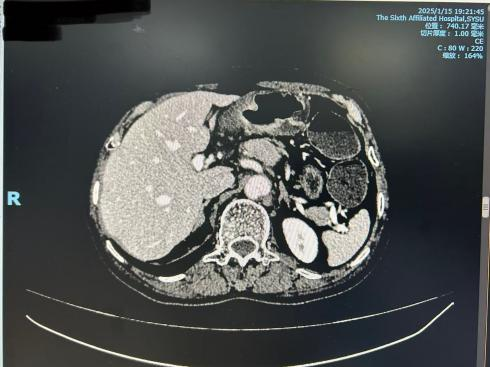

胸腹部盆腔CT平扫+增强(2025年1月15日):胃体、胃窦部胃壁不规则增厚,胃周多组淋巴结(3、5、7)肿大,考虑胃癌并淋巴结转移可能性大。拟CT分期为cT4N2M0。

图1. 胸腹部盆腔CT平扫+增强

初步诊断:胃恶性肿瘤(中-低分化腺癌),临床分期:cT4N2M0(dMMR)。